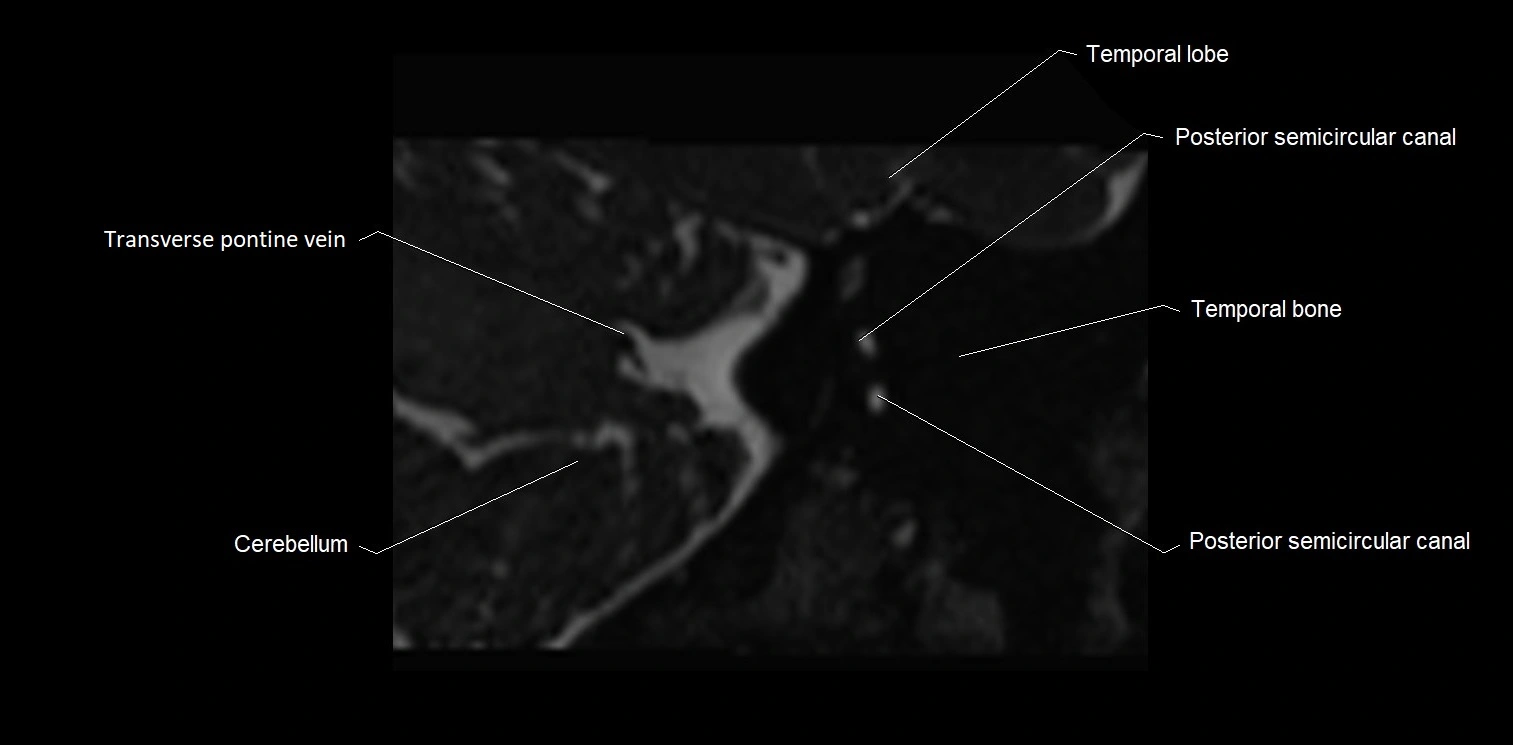

MRI images

image